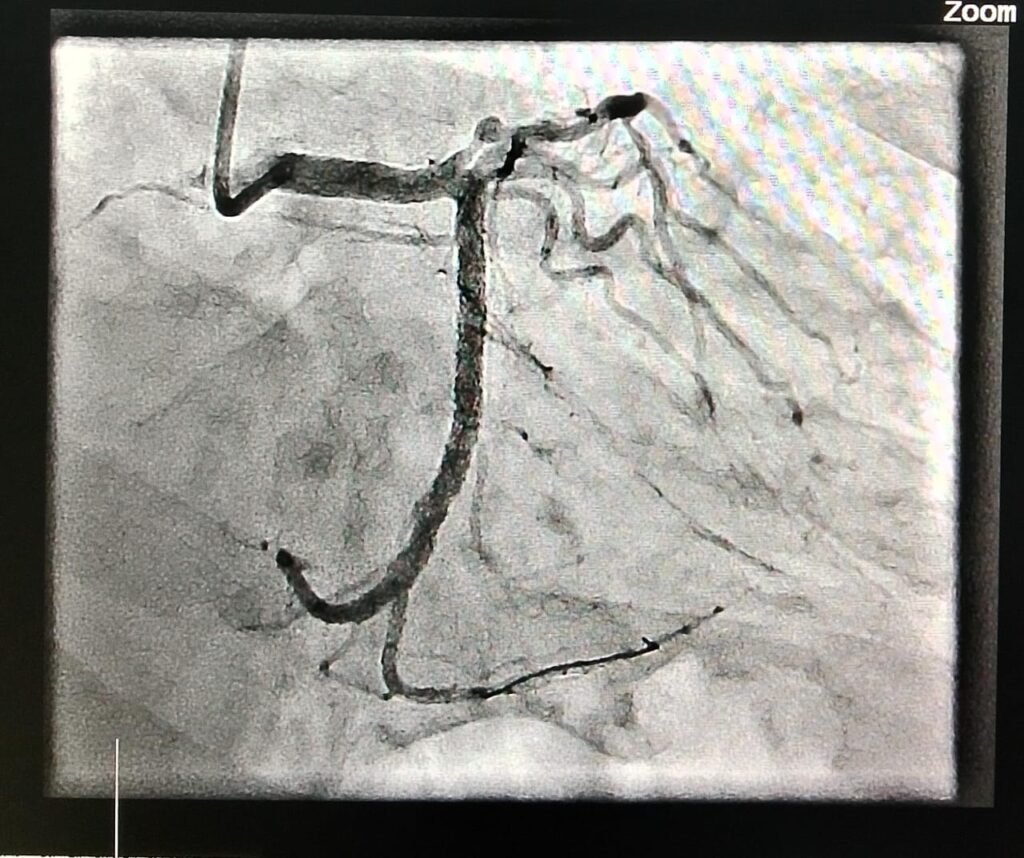

Coronary Angiography is a minimally invasive procedure that allows doctors to visualize the blood vessels of the heart to detect blockages, narrowing, or other issues. It is the gold standard diagnostic tool for assessing coronary artery disease and is typically performed when a patient exhibits symptoms like chest pain, shortness of breath, or unexplained fatigue. Angiography involves injecting a contrast dye into the coronary arteries and taking X-ray images to reveal any obstructions or irregularities in blood flow.

The process is performed in a specialized unit known as the catheterization lab or cath lab. During the procedure, a thin, flexible tube called a catheter is inserted into a blood vessel, typically in the wrist or groin, and guided to the coronary arteries. The dye is injected through the catheter, allowing the arteries to be seen clearly on the X-ray images. This helps doctors determine the severity and location of any blockages or narrowing in the arteries.